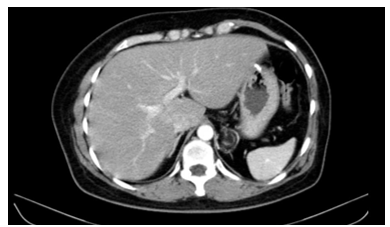

Chụp cắt lớp vi tính ổ bụng có tiêm thuốc: Vị trí bờ cong lớn dạ dày có nốt kích thước 21x15mm, phát triển ra ngoài dạ dày, không phá hủy lớp niêm mạc dạ dày, bờ đều ranh giới rõ, ngấm thuốc tương đối đồng nhất sau tiêm, không thấy hạch to lân cận.

Hình 4. Hình ảnh chụp CT ổ bụng: Nốt ở bờ cong lớn dạ dày kích thước khoảng 21x16 mm (vị trí mũi tên đỏ)